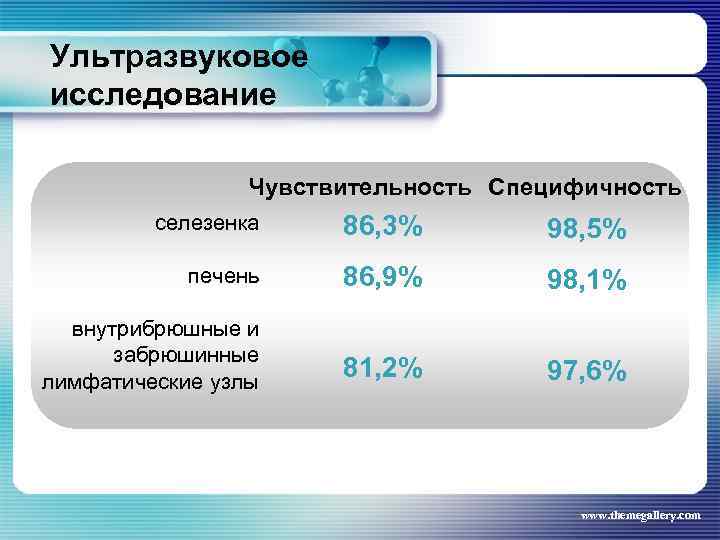

Ультразвуковое исследование Чувствительность Специфичность селезенка 86, 3% 98, 5% печень 86, 9% 98, 1% внутрибрюшные и забрюшинные лимфатические узлы 81, 2% 97, 6% www. themegallery. com

Ультразвуковое исследование Чувствительность Специфичность селезенка 86, 3% 98, 5% печень 86, 9% 98, 1% внутрибрюшные и забрюшинные лимфатические узлы 81, 2% 97, 6% www. themegallery. com